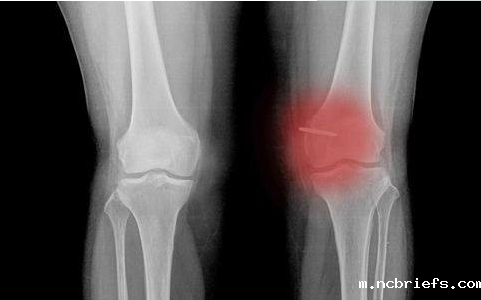

【摘要】:骨密度低不仅是老年人的专利,现在越来越多的年轻人也易骨密度低从而患上骨质疏松的症状,骨密度检测仪厂家小编提醒现在年轻人对于自身的骨密度检查不容忽视。那么骨密度低都有哪些症状呢,下面骨密度检测仪厂家小编给大家具体介绍下!

1、大概有超出75%左右的骨密度低的群体平常不自觉性的就会感觉背部疼痛,并且这类痛疼是顺着人体的腰椎慢慢向人体的两边扩散,当骨密度低的人仰卧起坐或是是坐着的时候痛疼的情况还可以得到减轻,可是假如长期站立则又会疼痛。

2、骨密度低的人常常在睡醒的时候或是是低头的那时候会觉得到肘关节部位不适感,乃至在用劲干咳的那时候满身的关节都会有涨痛的感觉。有某些长期骨密度低的人身椎体骨小梁会发生萎缩,并且锥体会渐渐地被缩小变形。

3、有一些骨密度低的人就算是到了成年人以后个子也会缩短,并且那样的人因此会伴随驼背的现象。这将会由于那股相对密度低造成骨质疏松症以后人体没法担负标准体重的负荷,这时就导致了脊椎锥体弯曲形变,最终造成身高缩短。